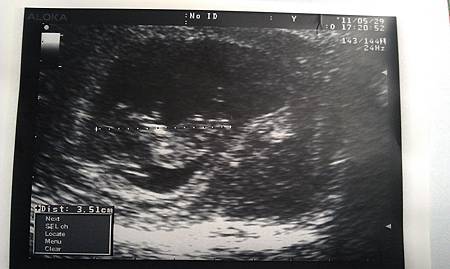

醫生也是照慣例幫我照照嚕..

隔了才不到幾天

肉肉有3.51cm,而且,我看到小手小腳在抖動了!!!!!

不瞞你說,這真的嚇到我了!!!

(我還是跟準老杯一起很冷靜的假裝沒事.....)